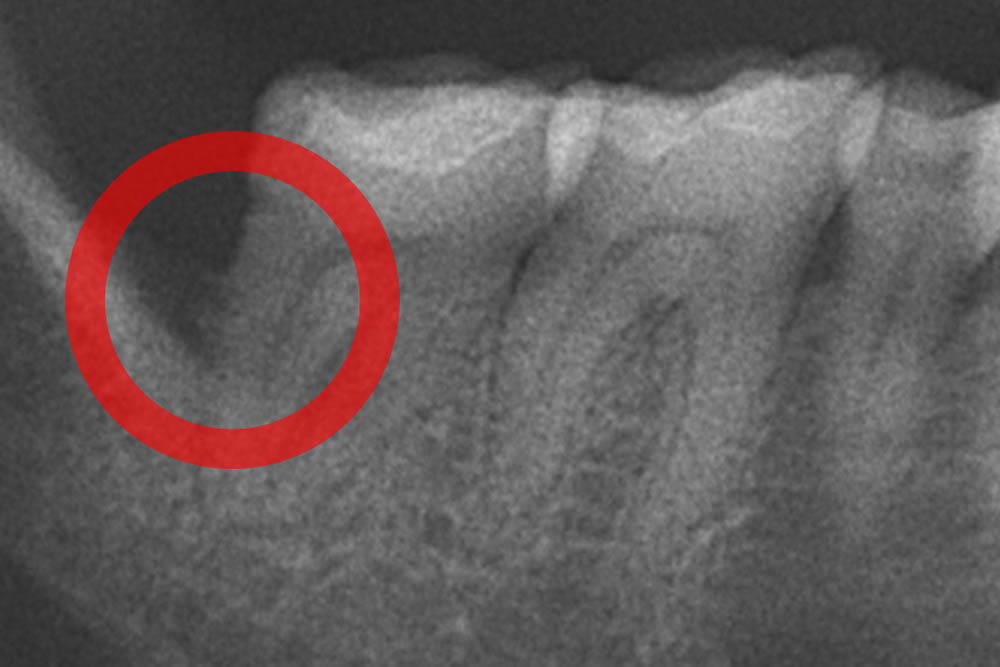

初診時パノラマレントゲン

奥歯を中心に歯周病による顎の骨の吸収、歯茎の奥深くの歯根に沈着した縁下歯石を確認しました。

右下のレントゲン写真の比較